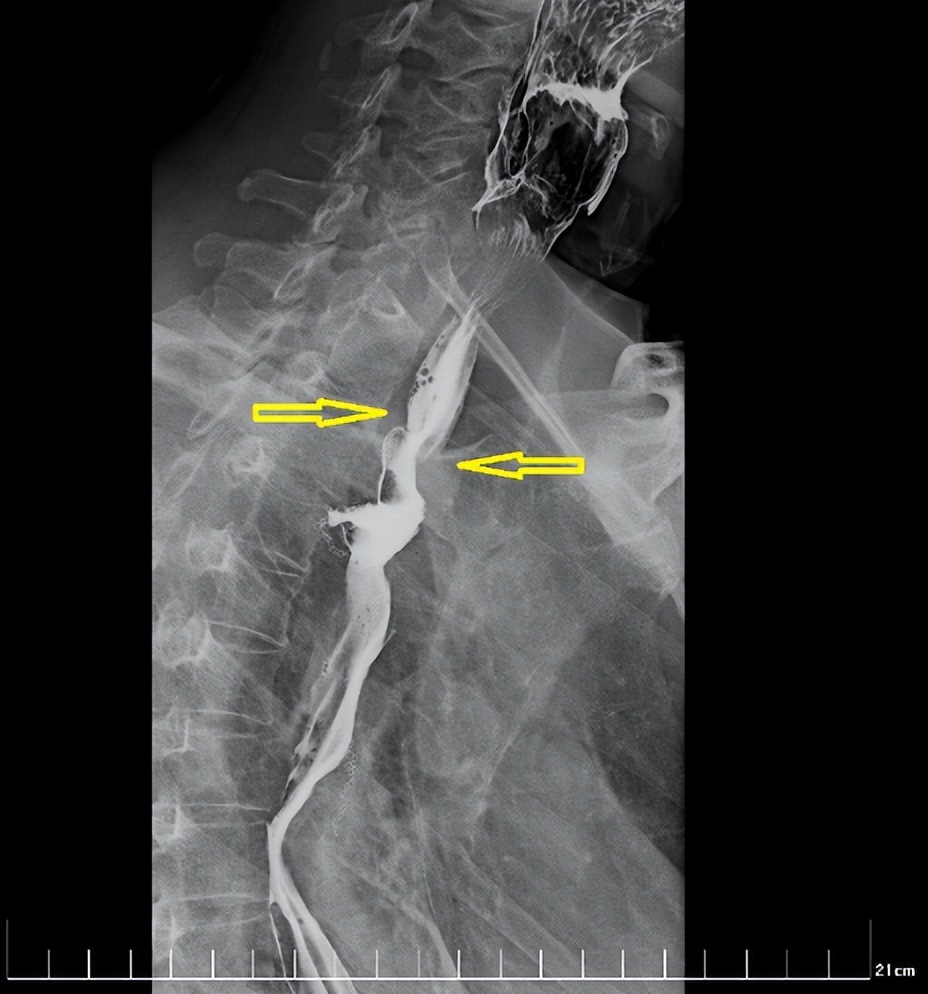

经过一个周期的放疗,李先生明显感受好多了,可以正常吃饭喝水。食管钡餐造影显示,食管吻合口区肿块明显缩小,食管狭窄减轻。

治疗前

治疗后